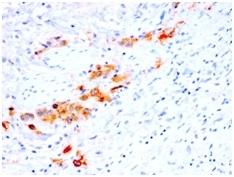

Positive Control

Cervix or Tongue Squamous Cell Carcinoma

IHC, FFPE (verified)

IHC (FFPE) (verified)